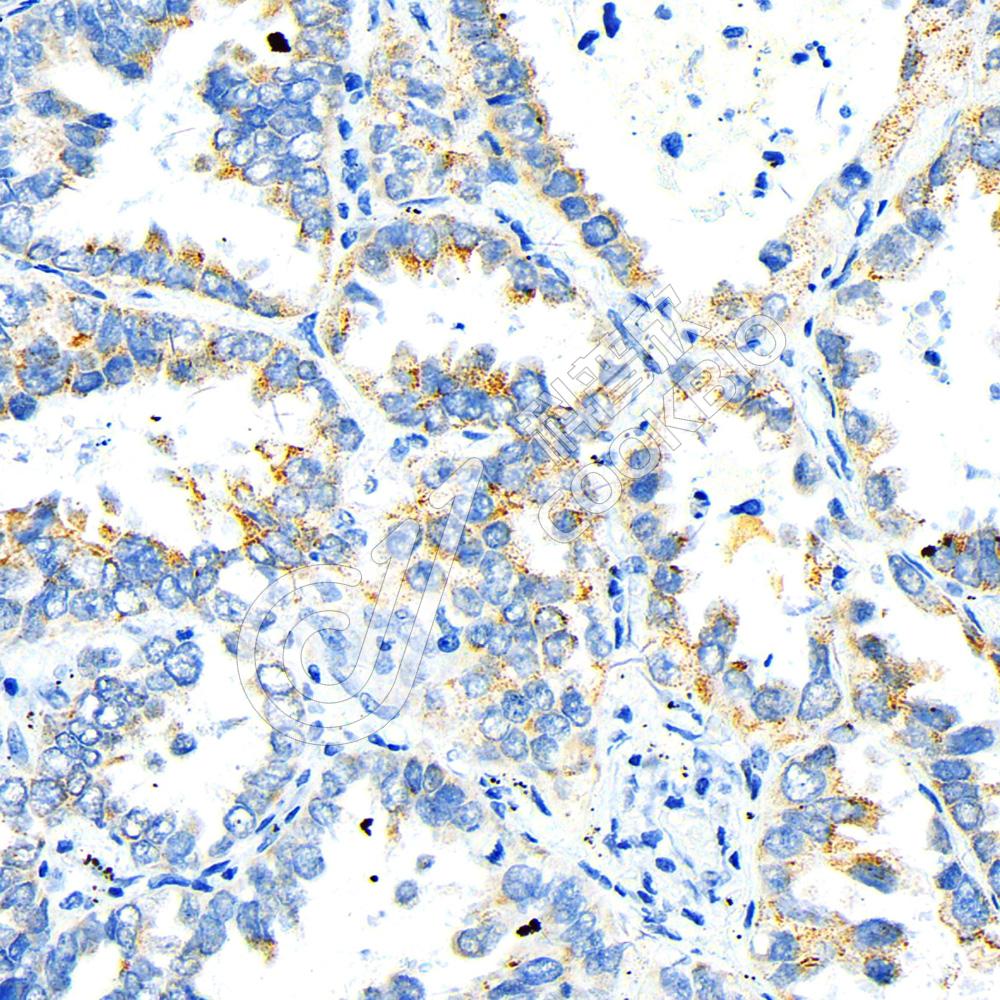

IHC检测EFS蛋白(货号 K1342339).

样品: 人肺癌, 4%多聚甲醛 (货号KSG1101) 固定12-24小时.

抗原修复: 柠檬酸抗原修复液(干粉, pH 6.0) (KSG1201), 98℃, 20分钟.

—抗: 1: 1100稀释, 4℃ 孵育过夜.

二抗: S-vision免疫组化多聚二抗(山羊抗兔),即用型 (货号KB3906), 室温孵育20分钟.